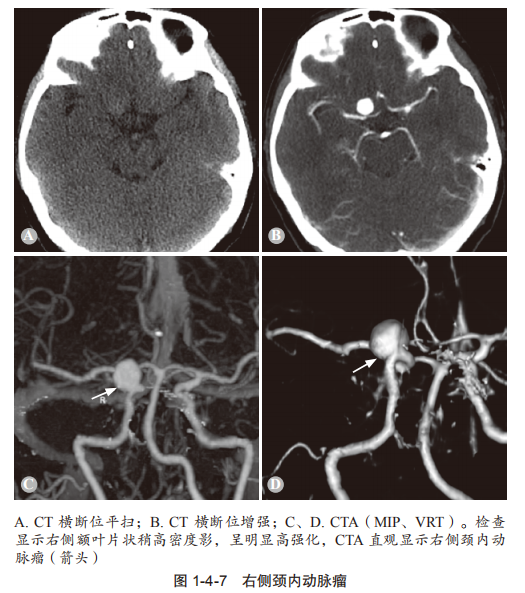

颅内动脉瘤是啥? 简单来说,就是脑动脉的某一段像吹气球一样鼓起来了。它通常长在血管分叉的地方,平时可能没啥感觉,但一旦“爆炸”(破裂),就会引发脑出血,后果非常严重! 谁更容易“中招”? 全球约3%-5%的人有颅内动脉瘤。 女性比男性更容易得(姐妹们要当心!)。 高发人群:高血压患者、长期吸烟的人、有家族病史的人,以及多囊肾患者风险更高。 破裂了会怎样? 每年1%-2%的动脉瘤会破裂,破裂后死亡率高达40%-50%!破裂时,人会突然感到“这辈子最剧烈的头痛”,还可能伴随恶心、呕吐、脖子僵硬,甚至昏迷或猝死。即使抢救及时,也可能留下神经功能障碍,比如手脚不灵活、说话不清楚等。 高医生遇到的真实故事 45岁的王女士,长期吸烟还有高血压。某天上厕所时,她突然感到一阵剧烈的头痛,接着恶心、呕吐,差点晕倒。送到医院后,医生发现她的颅内动脉瘤破裂了,引发了脑出血。经过紧急手术,她幸运地活了下来,但留下了部分后遗症。 这个案例告诉我们:早发现、早治疗,真的能救命! 没破裂时会有啥症状? 大多数时候没感觉,就像一颗“定时炸弹”,悄无声息。少数人可能会感到头痛、视力模糊、眼皮下垂或看东西重影。如果出现这些症状,别拖,赶紧去医院检查! 怎么检查? CT、CTA、MRI/MRA:这些影像学检查可以帮医生看清楚动脉瘤的位置和大小。 怎么治? 开颅夹闭术:打开脑袋,用夹子夹住动脉瘤的根部,防止它破裂。 血管内介入治疗:通过血管把弹簧圈塞进动脉瘤里,让它慢慢闭合。 具体用哪种方法,得听医生的建议。 怎么预防? 控制血压:高血压是动脉瘤的“好朋友”,一定要把血压控制在正常范围。 戒烟:吸烟会大大增加动脉瘤的风险,赶紧戒了吧! 健康饮食:少吃油腻,多吃蔬菜水果,保护血管健康。 定期体检:尤其是高危人群,做个脑部检查,心里更有底。

DSA(脑血管造影):这是诊断的“金标准”,但属于有创检查,一般用于确诊或手术前评估。